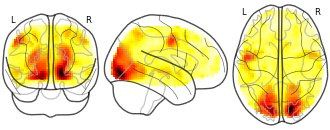

"name": "Multi_VBMgreater_fMRIenhanced",

"description": "Multi-modal analysis in BPD. Brain regions exhibiting greater gray matter and enhanced activation during emotion processing in BPD compared to healthy controls. Note: Results were thresholded at p<.0025. Note2: Results were updated (see Erratum for this publication).",